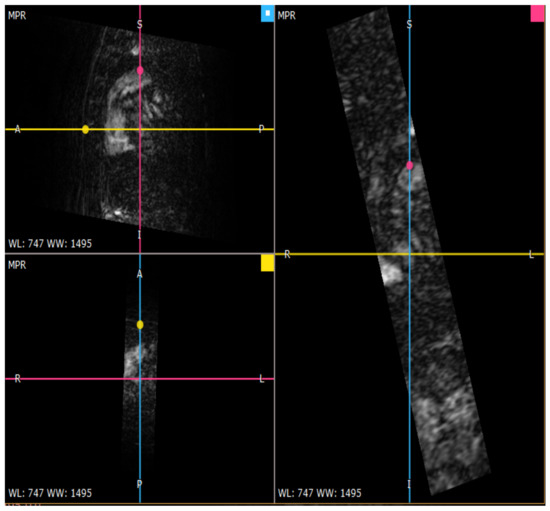

The multiplanar reconstruction in Figure 6 is a crucial step in the 3D reconstruction of the descending aorta presented in the axial plane in Figure 7.

Figure 6.

Multiplanar reconstruction of TRICKS cuts for the aorta.

Figure 7.

Model of the descending aorta in axial plane.